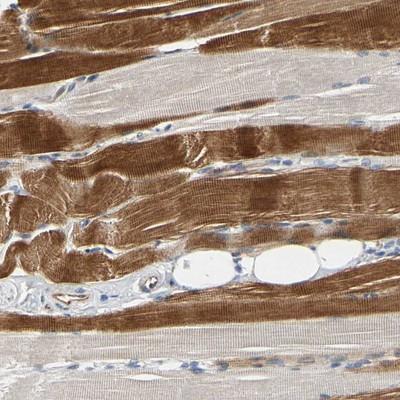

- Immunohistochemistry: ZNF236 Antibody [NBP1-86486] - Staining of human skeletal muscle shows moderate cytoplasmic positivity in myocytes.